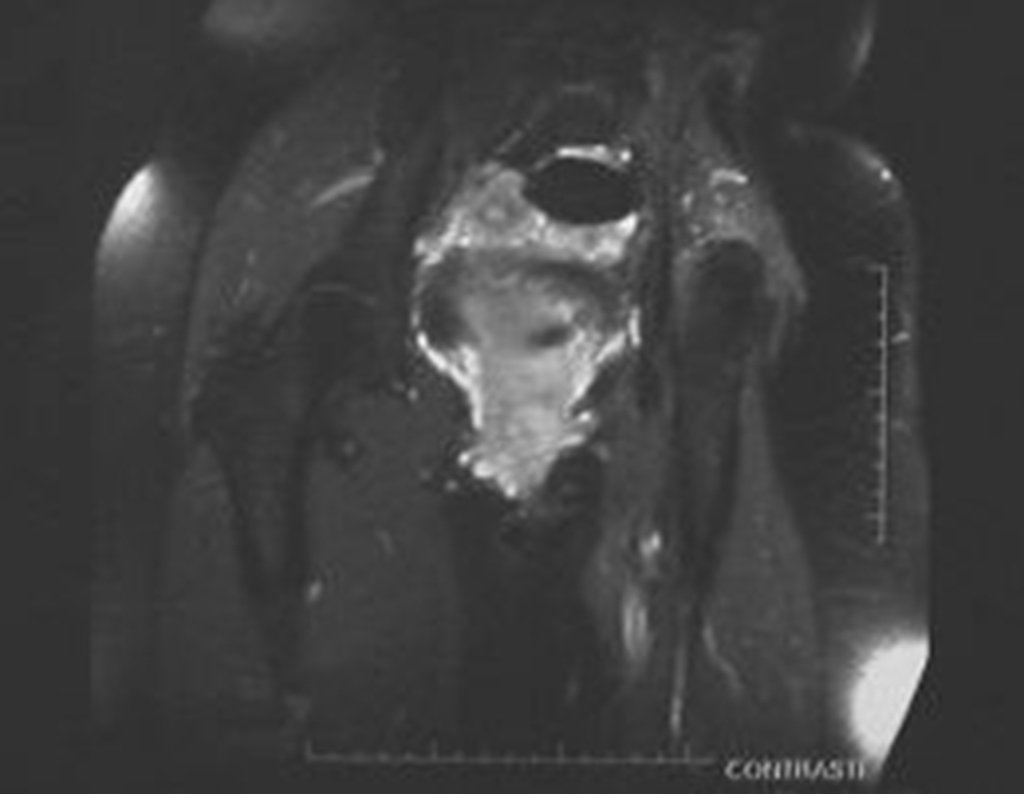

Condrosarcoma de pelvis – Pelvectomía interna total. Paciente femenina de 19 años que consulta por malestar y aumento de volumen en pelvis izquierda. Clínicamente se presentó dolor leve a la palpación del ala ilíaca, palpándose una tumoración dura y adherente. Respondido el 18 de diciembre de 2002, con los siguientes exámenes de imagen: 13/11/1983 18/12/2002.